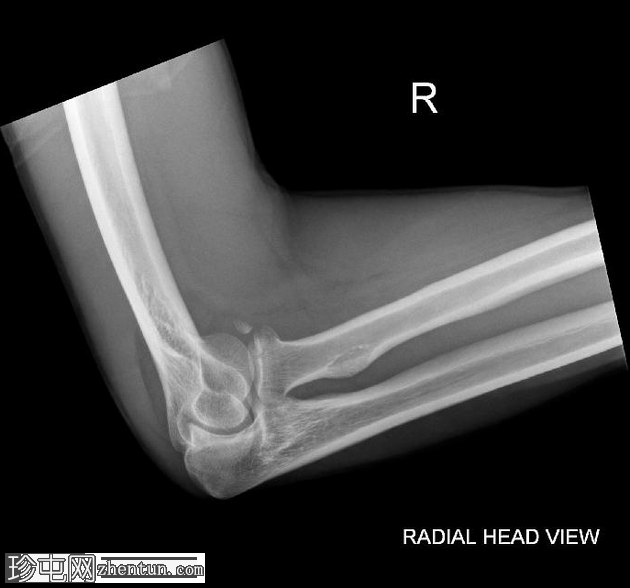

X光片

1.png

斜位片

桡骨头关节内粉碎性骨折,关节面轻微凹陷。肱骨远端前侧可见移位的骨碎片,桡骨头位片上清晰可见。可见前后脂肪垫征,提示肘关节积液。

未见肘关节脱位,肱桡骨小头排列保持正常。冠突水平可见复合阴影,可能与软组织重叠或投影伪影有关。桡骨和尺骨骨干外观完整,无骨折征。周围软组织肿胀。